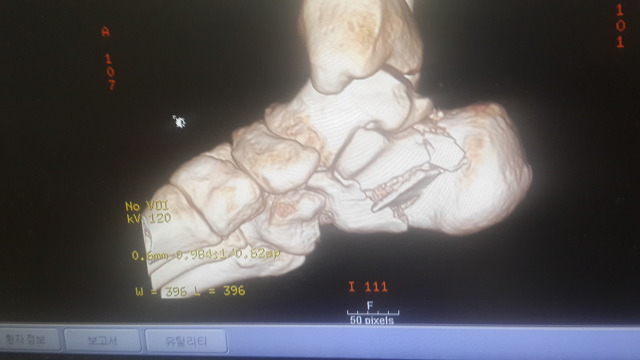

아래는 수술 전 찍은CT 와 X-ray 사진들입니다.

종골이 으스러졌다고 하시더라고요.